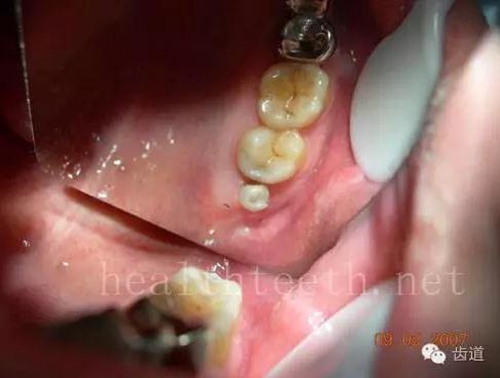

不良的根管充填治療

77.jpg